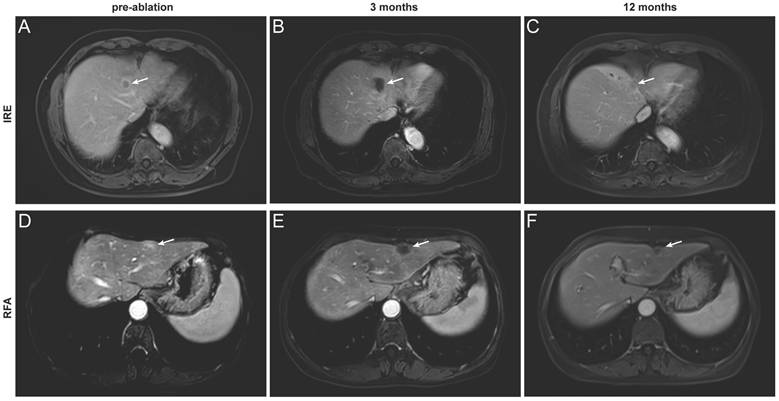

Assessment of treatment outcome

Based on the distinct ablation-zone remodeling patterns observed between IRE and RFA, clinical outcomes were further evaluated. LTP occurred in four patients after ablation, including three patients with secondary liver tumors and one patient with primary liver cancer (Table S1). The patient-level LTP rates were 18% in the IRE group and 15% in the RFA group (Table 3). For the primary endpoint, the median follow-up duration for LRFS was 40.5 months (range, 2-44.2 months). Kaplan-Meier analysis demonstrated no significant difference in LRFS between the IRE and RFA groups (Figure 4A). The LRFS rates at 6 months, 1, and 3 years were 90.9%, 81.8%, and 81.8% in the IRE group, respectively, and 100%, 91.7%, and 78.6% at the corresponding time points in the RFA group. Median LRFS was not reached in either group during the follow-up period. The overall ORR was 36.4% in the IRE group and 23.1% in the RFA group (Figure 4B). No significant differences were observed in PFS or OS between the two groups (Figure 4C, D). Representative cases are shown in Figure 5. Pre-ablation delayed-phase images depict the target lesions treated with IRE and RFA (Figure 5A and D). During follow-up, venous-phase images demonstrate well-demarcated hypoenhancing ablation zones at 3 months (Figure 5B and E) and 12 months (Figure 5C and F) after ablation, indicating complete lesion eradication.

Figure 5

Representative contrast-enhanced MRI images illustrating complete tumor ablation after IRE and RFA. (A-C) A 67-year-old man with hepatocellular carcinoma treated with IRE. Images obtained before ablation (A, delayed phase) and at 3 months (B) and 12 months (C) after ablation (portal venous phase); (D-F) A 64-year-old woman with colorectal liver metastasis treated with RFA. Images obtained before ablation (D, delayed phase) and at 3 months (E) and 12 months (F) after ablation (portal venous phase). The target lesion and ablation zone are indicated by arrows.

Int J Med Sci Image